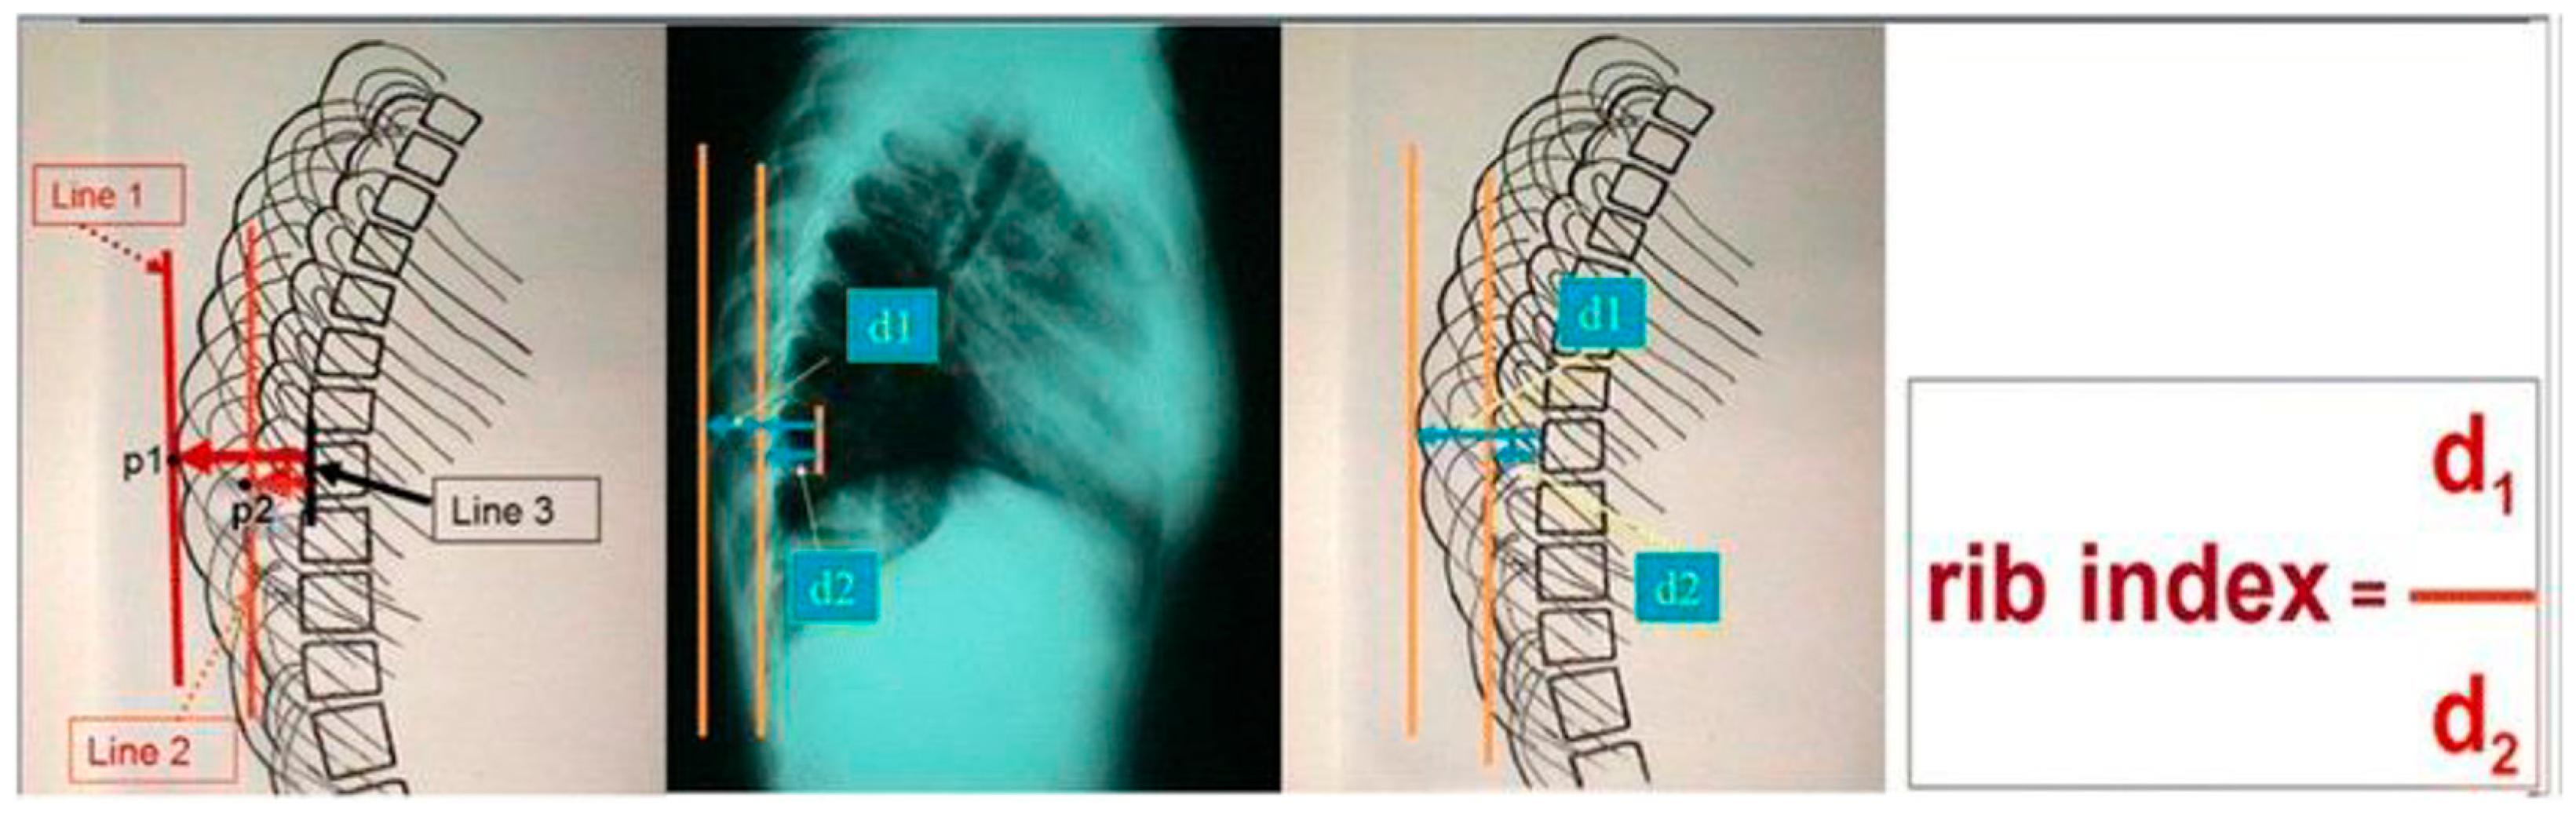

2. The Presented Sign and Index (DRCS and RI)

In Scoliosis Clinics at the Thriasio General Hospital of Greece, during the clinical assessment of asymmetric children referred for IS from the school scoliosis screening (SSS) program of the hospital with the Adams test, it was noticed by TBG that the contours of the two hemithoraces were always overlapping one over the other; in other words, they were shown to be asymmetrical in the lateral spinal radiographs. This observation was systematically noted, no matter if the spines of these children were found scoliotic or not in the prescribed radiographs. This overlap was coined the “double rib contour sign” (DRCS) [9], as shown in Figure 1. Consequently, the need for quantification of the degree of this overlap, which is the asymmetry of the DRCS—in other words, the thoracic deformity in the transverse plane—triggered the introduction of the RI [9], as shown in Figure 2. The use of the index prevents metric errors due to the varying magnifications of the films depicting the thorax. This novel sign and index were presented in Greece in 1999 and in France in 2000, and published in 2002 [9,10,11]. However, this publication [11] focused merely on the implications of the DRCS in the etiology of IS.

Figure 2.

The rib index (RI) of the thoracic cage in a standing spinal radiograph (from citation no. [12]).